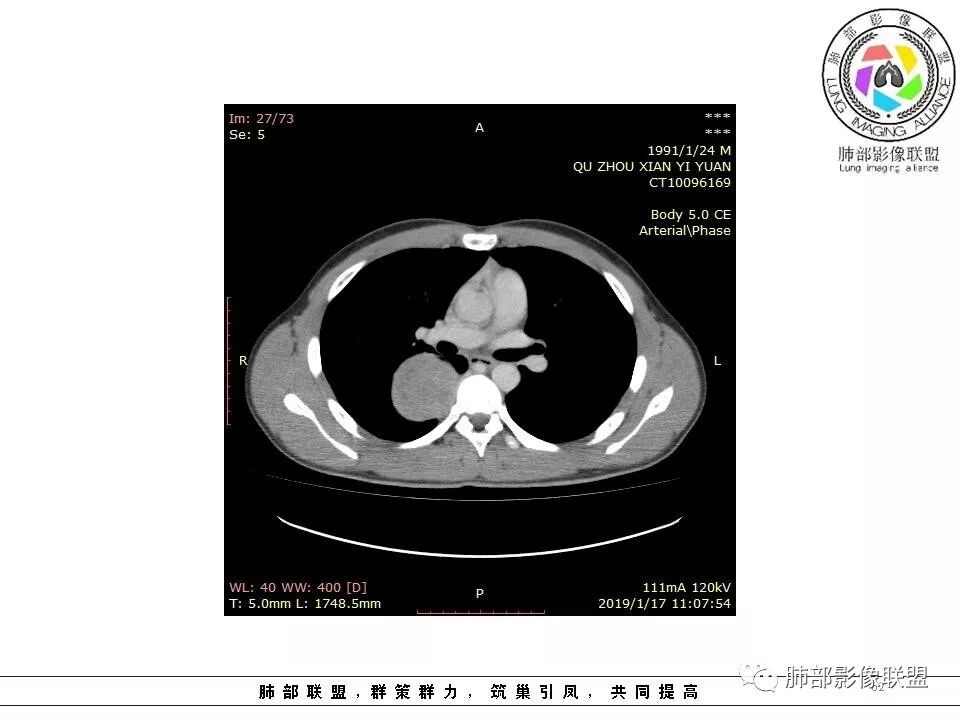

青年男性,间断胸痛;右侧脊柱旁可见一类圆形软组织密度影,密度欠均匀,增强扫描呈轻中度持续强化,邻近肺组织及肺动脉推移,可见肋间动脉供血,部分胸膜下脂肪可见,部分层面似见与右侧椎间孔相连。考虑后纵隔神经源性肿瘤。

青年男性,右侧脊柱旁软组织肿块,边缘膨隆,密度不均,临近肺组织受压、胸膜增厚,增强后动脉期呈不均匀强化,并可见肋间动脉供血,延迟期强化较均匀,定位肺外,首先考虑SFT,神经源性肿瘤待排

右肺占位,跨越上叶后段、下叶背,边缘光滑,瘤肺界面清,见肺压缩缘(线样不张`强化),见胸膜尾征,胸膜下脂肪未见明显增厚,肋骨丶脊柱未见侵袭及受压,渐进性丶地图样强化,冠状位似见体循环供血

右侧后纵膈肿块,有胸膜尾征,周围肺组织及支气管被推压,定位肺外,脏层胸膜来源,血供来自肺动脉或者支气管动脉,增强后持续渐进强化,蛇纹征,考虑SFT,鉴别鞘瘤。

青年男性,右后上纵隔脊柱旁沟可见团状软组织影,边界清,密度尚均匀,推挤邻近肺组织,胸膜可见掀起,有肺动脉供血,增强轻度蛇皮样强化,纵隔淋巴结未见肿大,邻近骨质未见破坏,胸膜下脂肪间隙消失,考虑SFT孤立性纤维瘤可能性大,鉴别神经鞘瘤,节细胞瘤,建议活检。

青年男性,胸痛,右上纵膈脊柱旁肿块,形态光整规则,支气管被推移,临近的胸膜明显增厚,有胸膜掀起,增强后密度不均匀,可见蛇形血管征,血供似乎有两根血管供血,考虑SFT

右上肺野脊柱旁软组织肿块,边缘光滑整齐,肺组织及气管右肺上叶支气管受压前移,外移,边缘可见胸膜尾征,病灶内密度不均,增强后渐进性持续强化,其内可见明显蛇纹血管征,首先考虑肺外来源,sft.可能性大

1.右上胸内脊柱旁类圆形肿块,质地似乎比较坚实,密度稍显不均,但未显示明确的坏死。

如此密度形态的病灶位于肺边缘首先应当想到孤立性纤维瘤,可相邻胸膜未见明显的异常强化和胸膜方向延伸。

注意所谓“胸膜尾征”的概念及形成机制与“脑膜尾征”是大不相同的。

3.相邻椎间孔未见扩大,也未见块影延入椎管,易起自于神经根的鞘瘤似乎找不到支持点。

可惜未提供矢状位骨窗图像,如在肋骨内下缘观察到压迹有助于肋间神经的鞘瘤的判断,这是因为二者之间密切的毗邻关系。

4.静脉期轻度不均匀强化,注意不是环形强化,亦未见明确的“AB区”,这点也不支持神经鞘瘤。临床及病灶轻度强化都不支持副节瘤。

尽管神经纤维瘤的诊断确实有些出乎意外,但病例开阔了我们的视野。